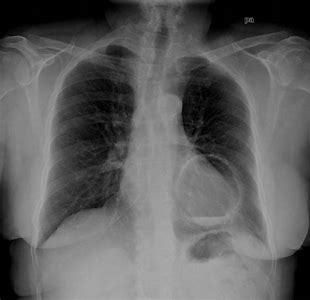

Bilateral air space opacification

• Diffuse air space opacification

• loss of silhouette sign

• air bronchograms

A

1. Cardiogenic

2. Non-cardiogenic